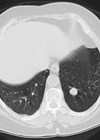

The accuracy of CT for local staging of bladder malignancy is only 40-60%, but it has a high sensitivity and specificity of over 90% for the diagnosis of bladder malignancy in patients with haematuria [3]. It is usually performed to assess the upper tracts as synchronous upper tract tumours are seen in 2.5% patients with bladder malignancy, and following cystectomy an upper tract TCC is seen in 1.8-6% cases.

Images should be obtained that allow full assessment of the urothelial system and assessed for any urothelial thickening, filling defect or irregularity. As with ultrasound, small flat bladder tumours may not be appreciated on CT, particularly if the bladder is not adequately distended. Tumours at the bladder base can also be difficult to see, particularly if the patient has an enlarged prostate.

CT also allows assessment of any nodal or metastatic disease, evaluation of the distal ureters and identification of any anatomical variants, such as duplex kidney and ureteric insertion, which should be identified prior to cystectomy.

CT is the main imaging modality for follow-up and should include assessment of the upper tracts to assess for an upper tract TCC. There is currently no agreed consensus about the frequency or timing of CT follow-up in patients with bladder malignancy.